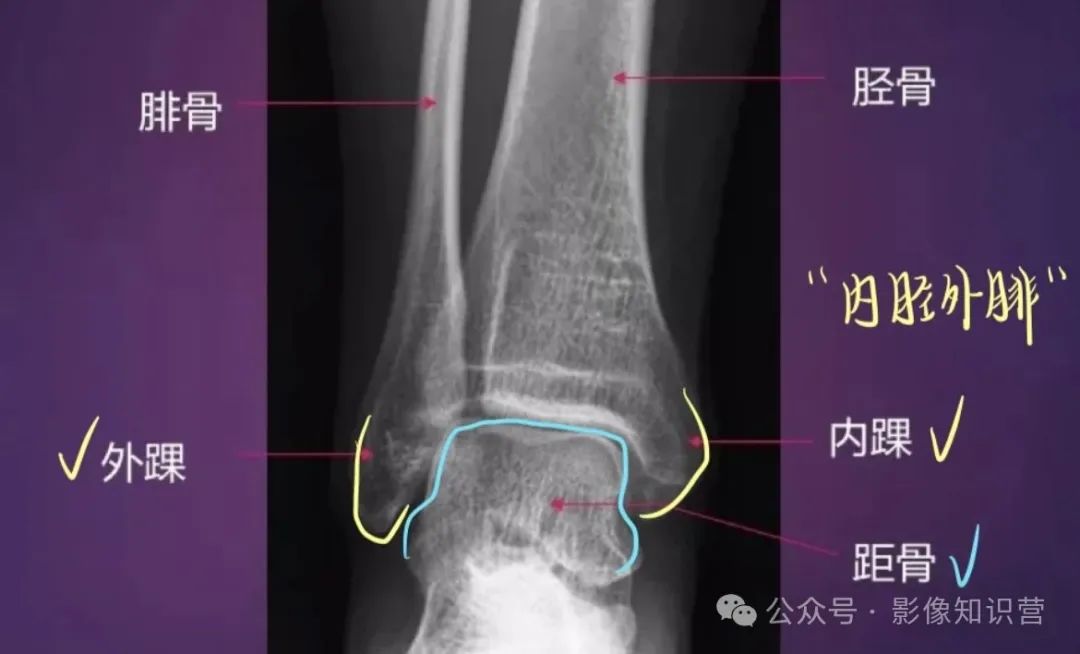

胫骨:位于小腿内侧,是小腿主要的负重骨。胫骨上端膨大,有内侧髁和外侧髁,两髁之间有髁间隆起。胫骨体前缘锐利,下端内踝是重要的体表标志。

腓骨:位于小腿外侧,较细。上端为腓骨头,下端为外踝,外踝比内踝略低。

踝关节

骨骼组成:胫骨远端(内踝)、腓骨远端(外踝)、距骨。

影像特征:X线正侧位:观察踝穴(距骨与内外踝的匹配)及下胫腓联合宽度(正常<6mm)